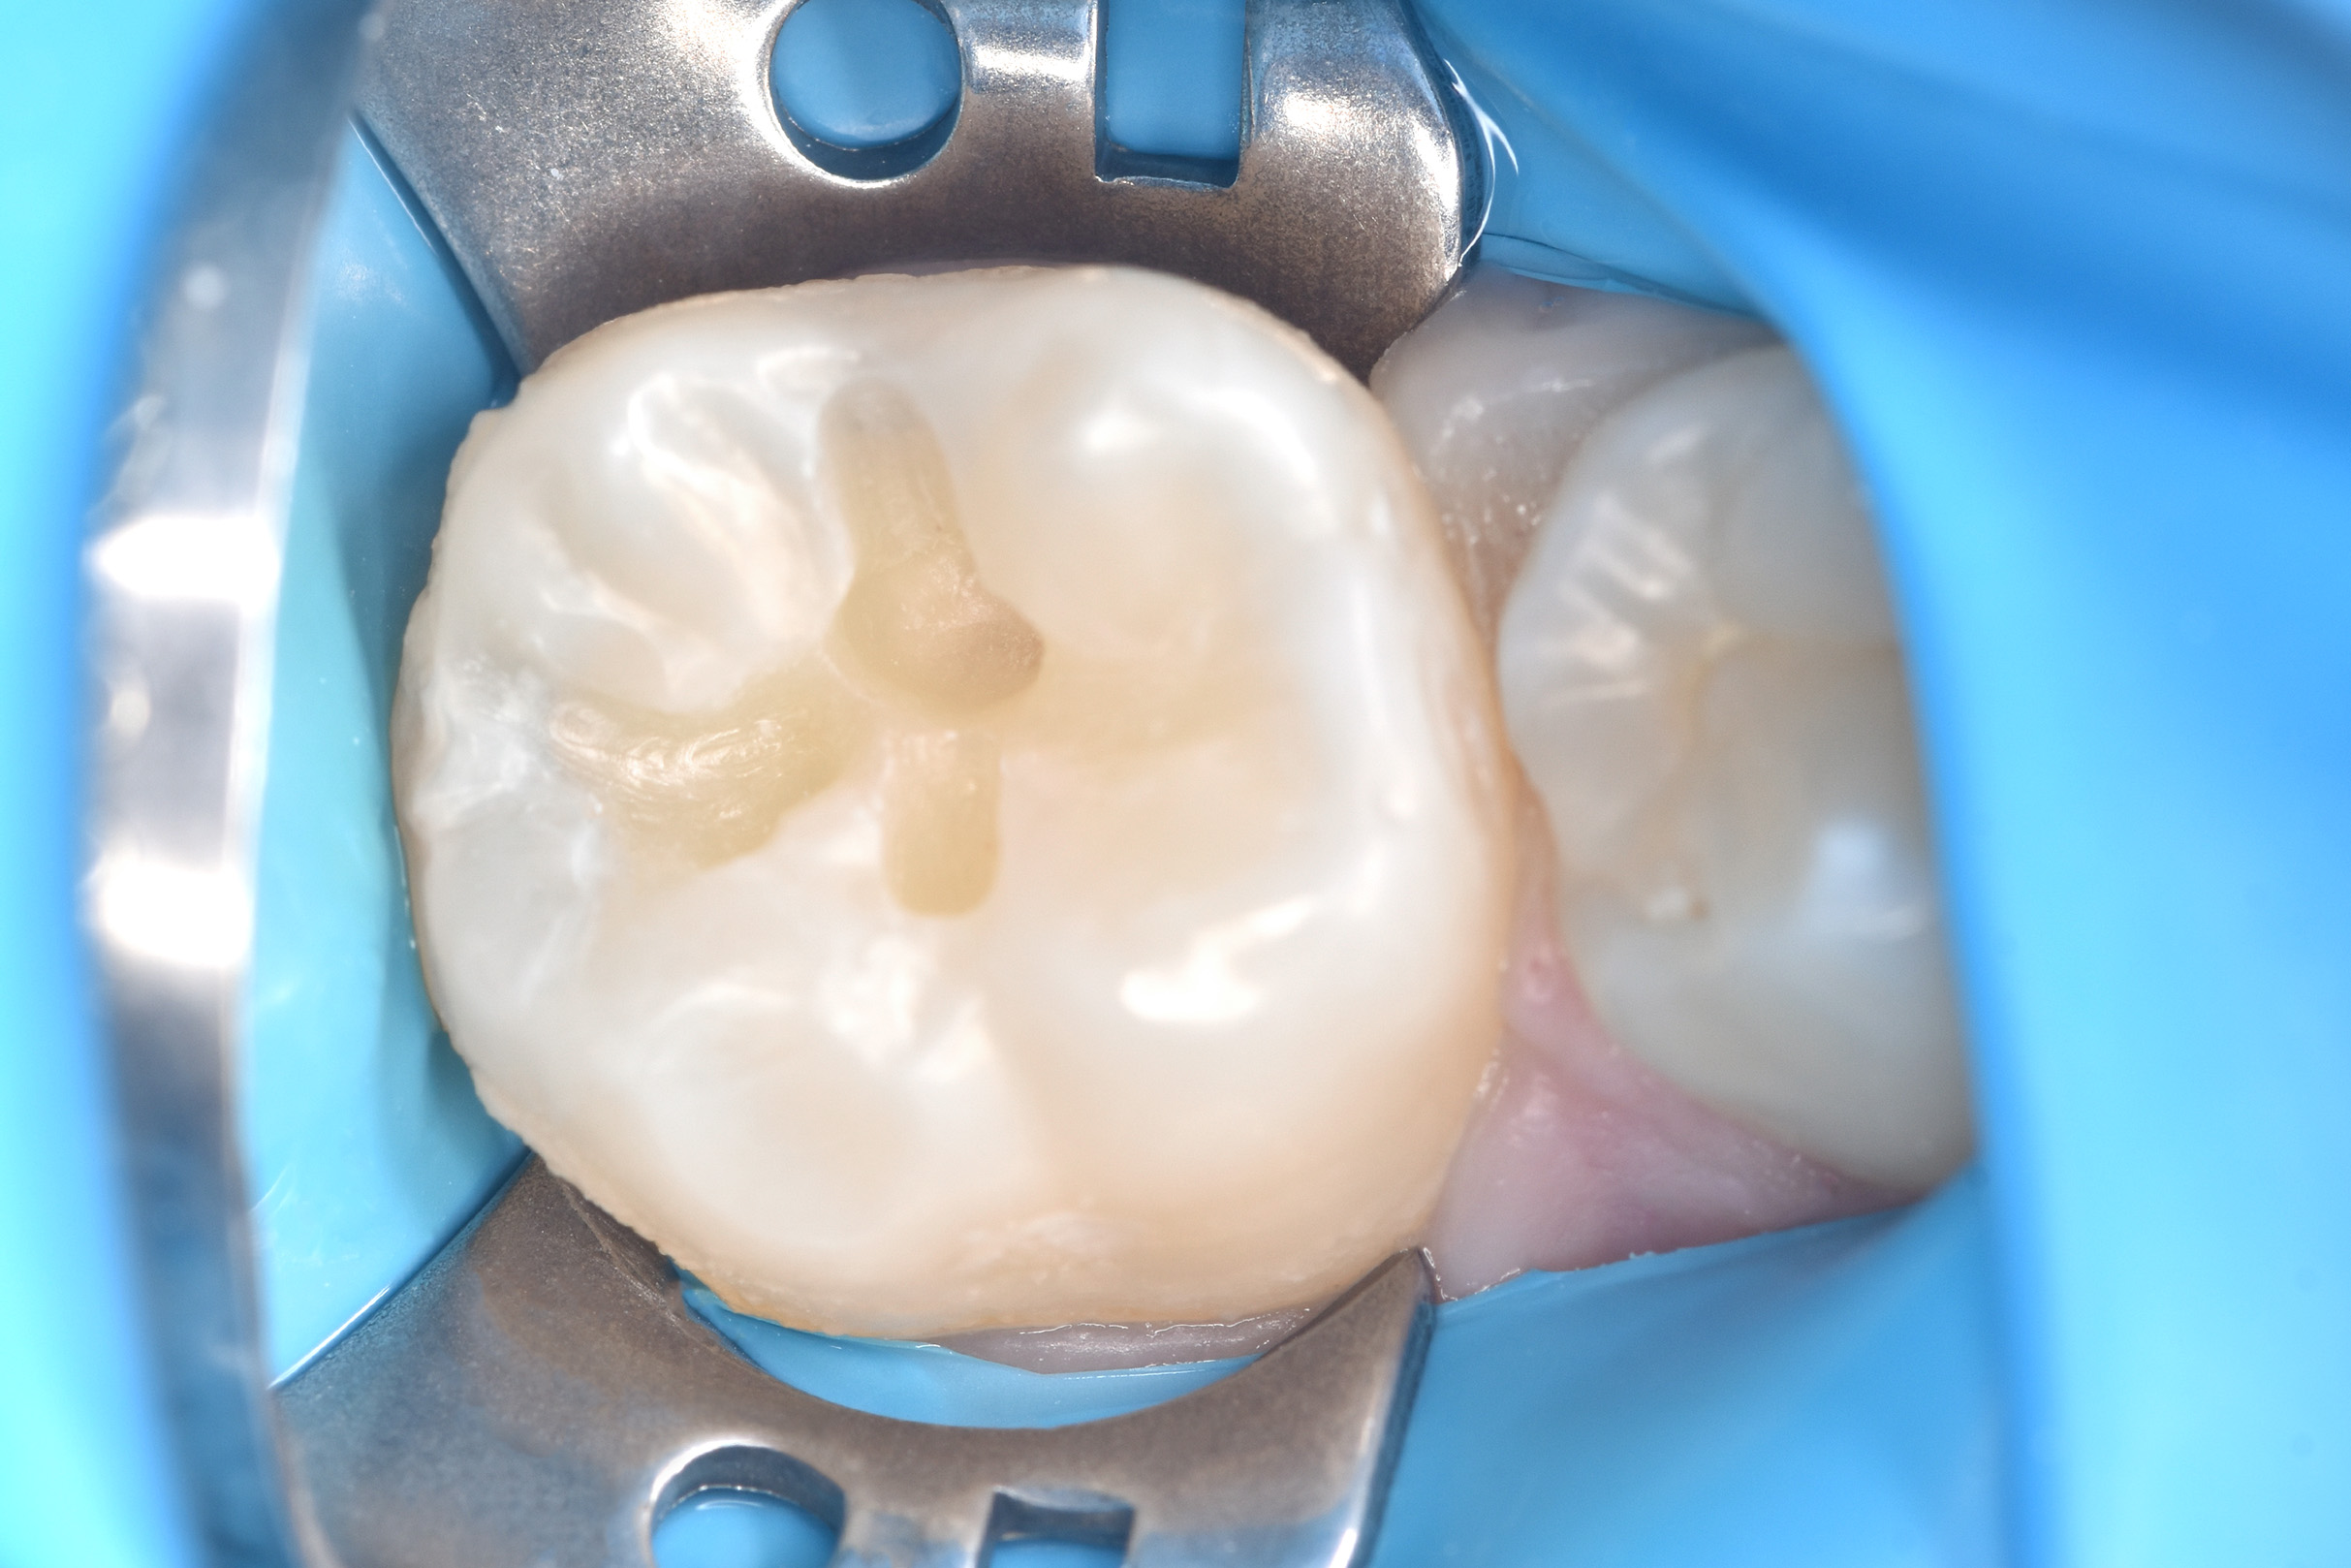

При осмотре выявлен кариес на 36 зубе.

36 зуб вылечен, восстановлен пломбировочным материалом.